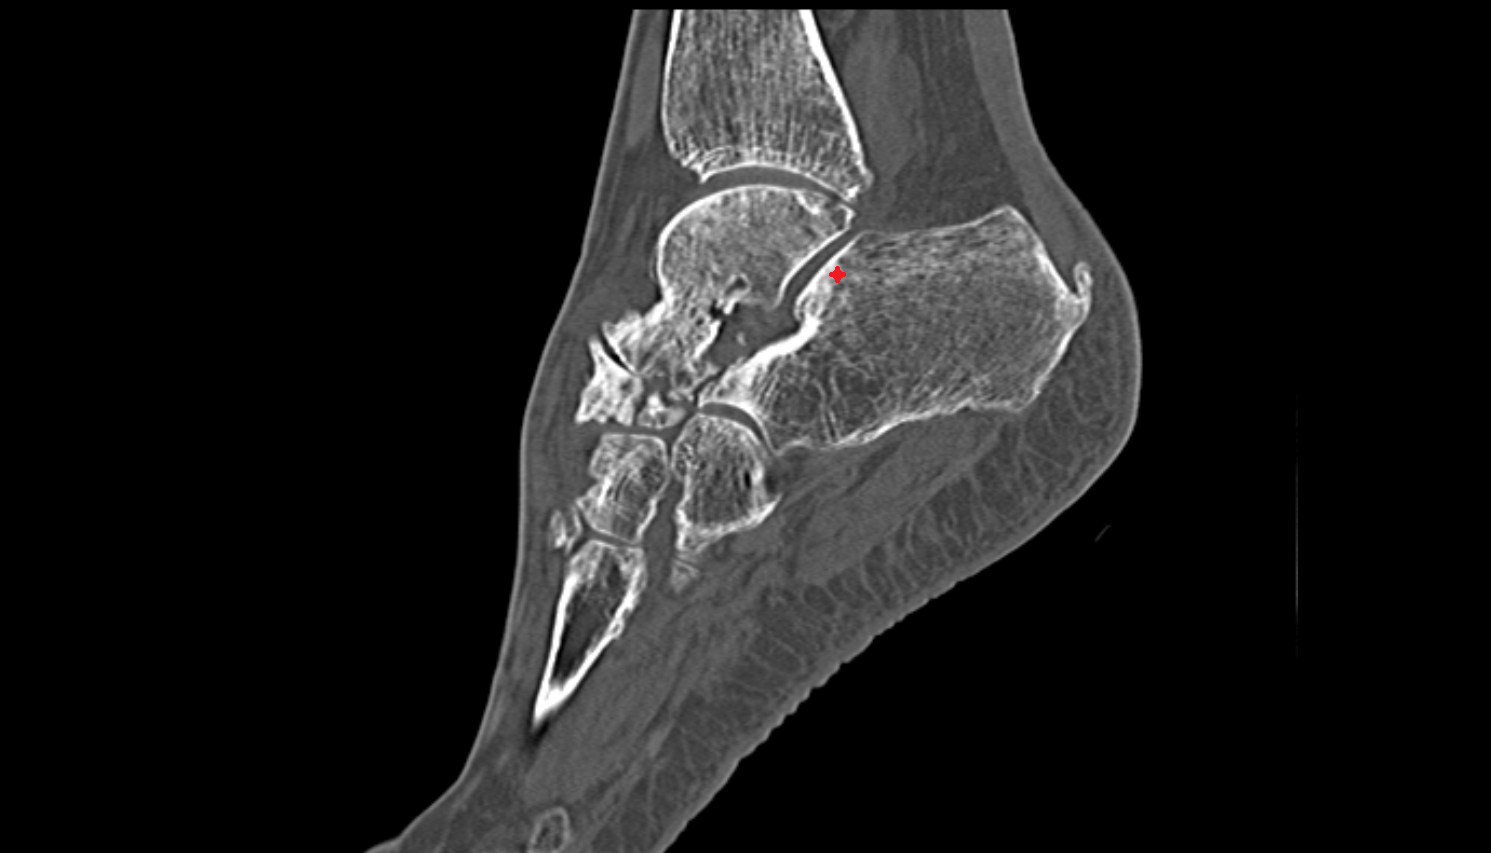

- Talus

- Head of talus

- Body of talus

- Neck of talus

- Calcaneus

- Ankle joint

- Talocalcaneal joint

- Talocalcaneonavicular joint